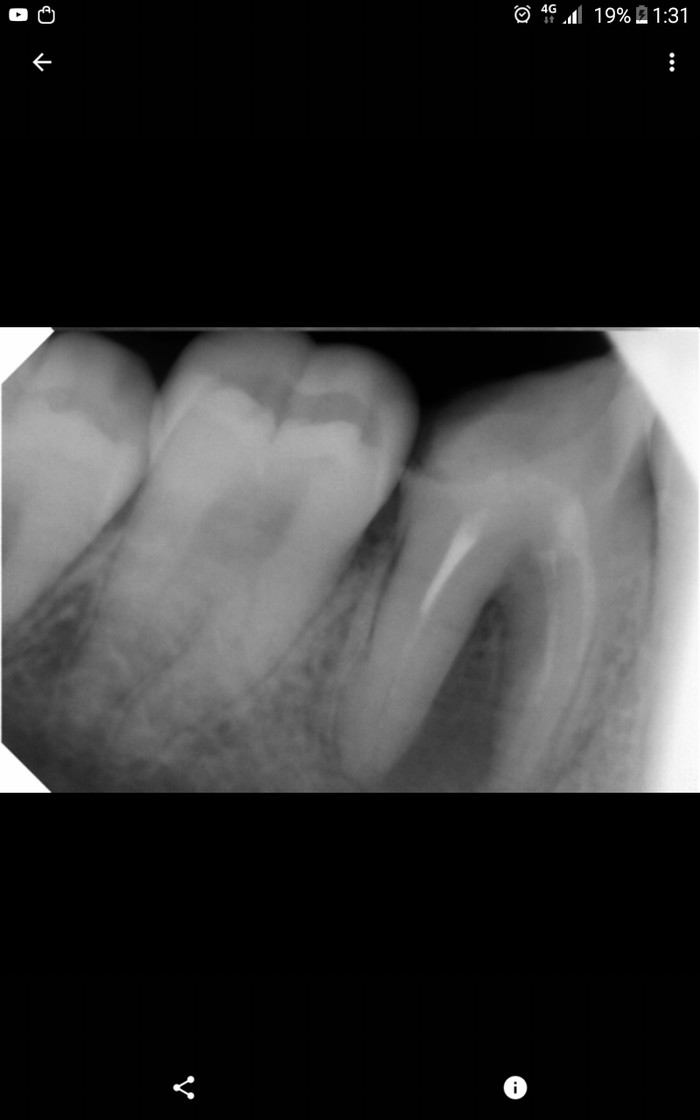

Сейчас мне уже 20 лет. В июне начались боли в области 47, абсолютно здорового зуба. Я пришла в частную клинику. Врач сначала не смог понять из-за чего боли, пока я не попросила его сделать снимок предыдущего. От увиденного он был в шоке... Канал не был закрыт до конца пломбой, и там такое начало развиваться. Врач заложил лекарство, поставил временную пломбу, зуб красиво прорезался, боли прекратились. А сверху есть зуб, который нессимертично разломался, а там остался острый край, которым я и разбила временную пломбу. Боли начались такие сильные, да ещё и канал оказался голым. Десна отекла, так что лицо потеряло симметрию. Есть неудобно, ибупрофен не помогает. Я побежала в госбольницу с острой болью. Зубной врач сказал, что неизвестно выживет зуб в этой схватке или не выживет.

Я этой малоприятной историей удивила всерьёз лежащего врача, и он, сделав новый снимок, вынес Вердикт - зуб под снос.

P. S. Следующее фото это фото после, а фото ниже, это то, с чем я пришла к стоматологу.